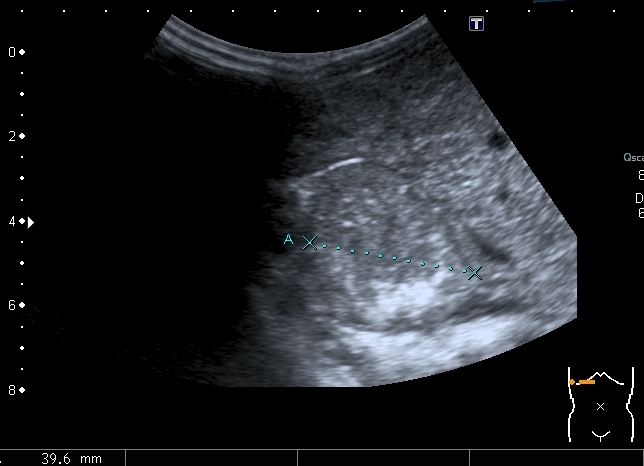

Левая доля

Левая доля прилежит к селезёнке, оттесняет её вниз и дорзально

Паренхима печени -гиперэхогенная , неоднородная, практически полностью замещена нодулярными образованиями, некоторые из них с "гало" и кальцификацией